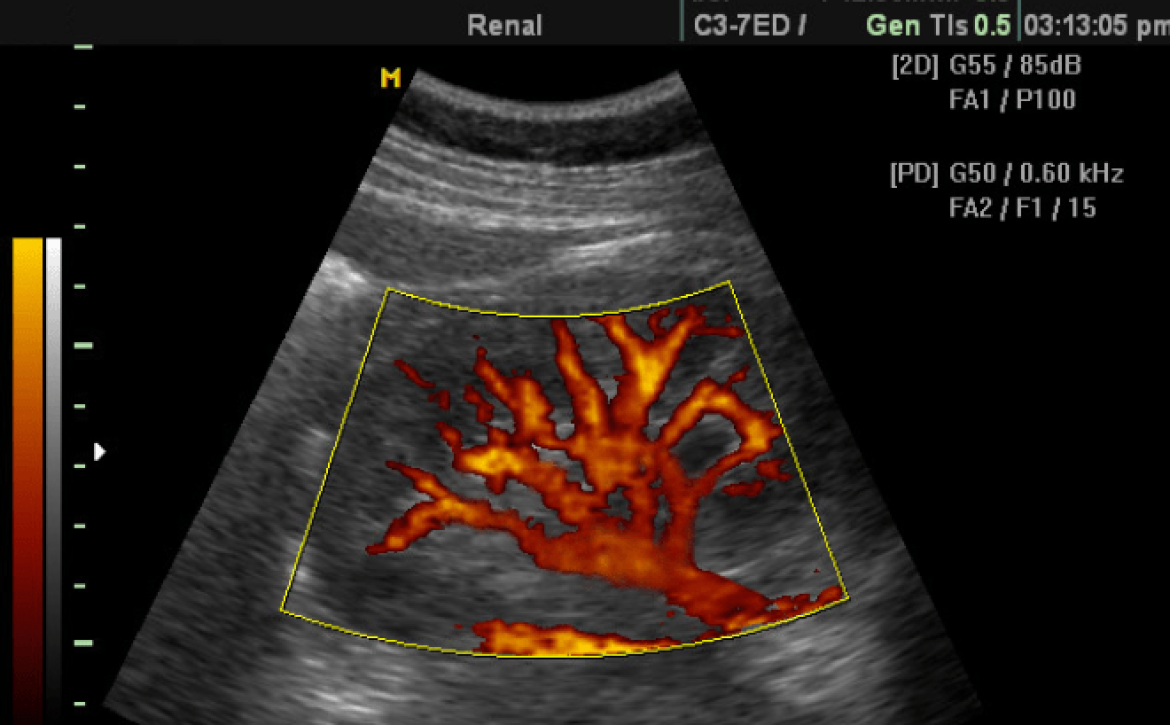

Ecografía doppler

¿Conoces todo lo referente a la ecografía doppler?

en el artículo de hoy queremos informarte de todo lo referente a esta ecografía, es importante que al momento de quedar embarazada o si ya estas en estado sepas cuales son los exámenes que debes realizarte para corroborar que todo con tu bebé va súper bien.

Existe un tipo de ecografía especial llamada Doppler.

Al igual que los ultrasonidos en una ecografía normal, con su rebote sobre las estructuras a revisar, nos devuelve una imagen, en el caso del Doppler estas ondas medirán la dirección y la velocidad del flujo de sangre que se quiera observar.

Esto resulta de mucha utilidad en el embarazo, dependiendo de los vasos que estudiemos, podremos detectar problemas en el feto o realizar su seguimiento. Por ejemplo uno de los vasos estudiados con más frecuencia son las arterias umbilicales , la arteria cerebral media, el ductus venoso o la vena umbilical. De ellas se obtienen una serie de parámetros que nos ayudaran a determinar el compromiso del bebé.

¿Qué revela la ecografía doppler?

La ecografía doppler, totalmente inocua e indolora tanto para la mamá como para el bebé, permite analizar datos muy relevantes del embarazo:

Evaluación y medición del flujo sanguíneo de las válvulas y las cavidades del corazón del bebé.

Análisis de las arterias del útero de la madre. Ello es especialmente relevante si la embarazada padece tensión alta.

• Observación de las arterias umbilicales del feto para determinar si el flujo sanguíneo que llega al bebé es el adecuado.

• Observación del flujo sanguíneo de las arterias cerebrales del feto.

Control de ciertas complicaciones del embarazo: hipertensión, diabetes gestacional, problemas en la placenta, retraso en el crecimiento, sufrimiento fetal, malformaciones cardíacas del bebé.

Es posible que, cuando te entreguen los resultados, te den una ecografía con distintas áreas de colores, que son los que representan el flujo sanguíneo. Los colores en cuestión van desde el rojo hasta el azul. El rojo indica que el flujo va en dirección a la sonda del ecógrafo (cuanto más intenso, más veloz es), mientras que el azul indica que el flujo se aleja de la sonda del ecógrafo (cuanto más intenso, más rápido se aleja). El blanco o amarillo suele indicar un flujo más lento o estable.